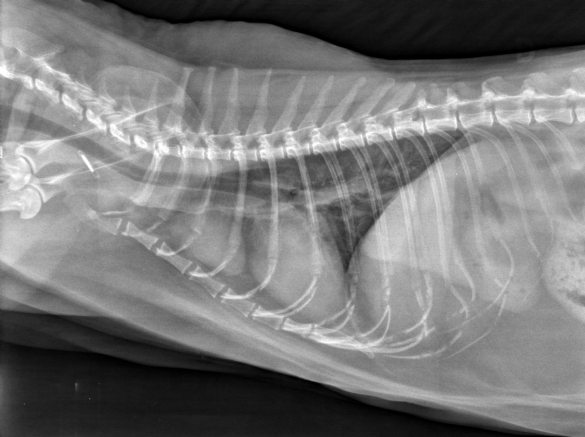

Mercredi 2 Septembre 2020 Animaux de compagnieVue latérale droite du thorax.

Un chat européen de 11 ans est présenté suite à la découverte fortuite d'une masse médiastinale (voir photo) afin de réaliser un scanner.